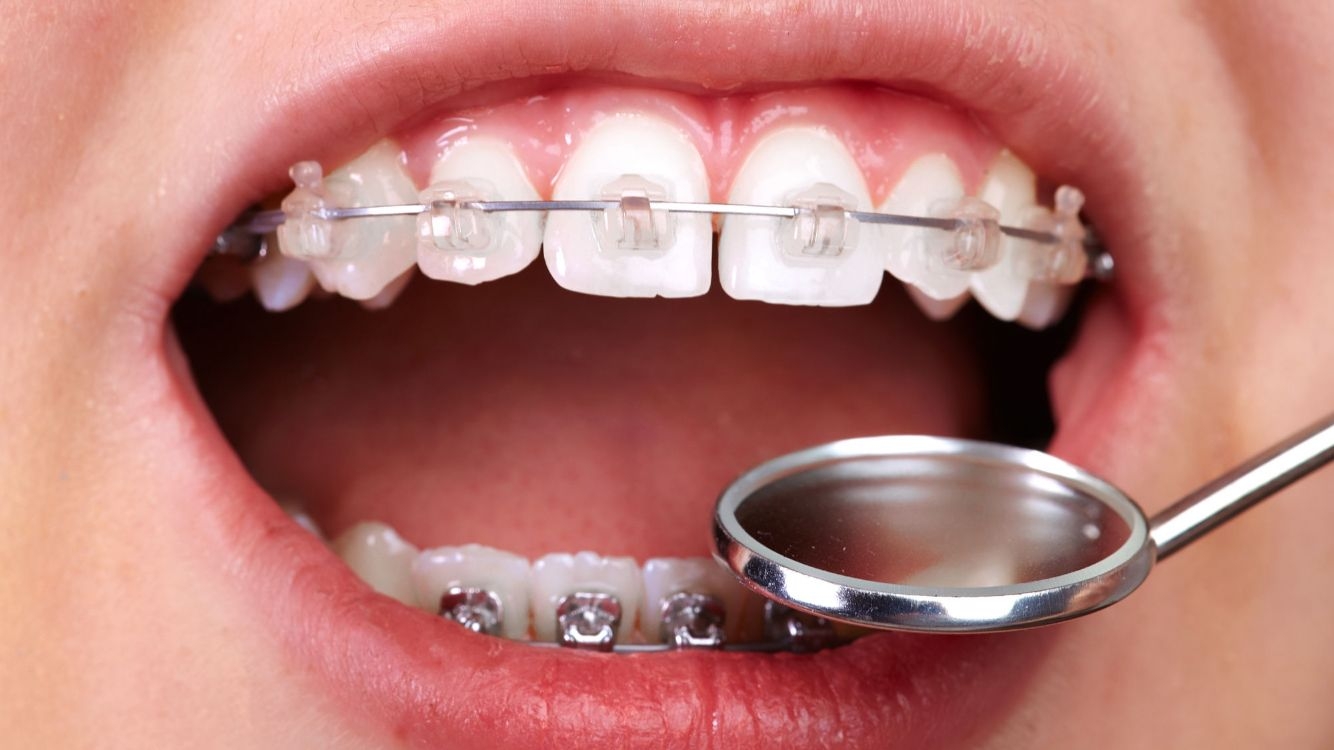

Los aparatos fijos, conocidos como brackets, son los encargados de mover los dientes mediante la aplicación de fuerzas suaves, transmitiendo al diente la tensión adecuada mediante un arco metálico (alambre generalmente de Ni-Ti) introducido en ellos. Estos brackets pueden ser metálicos, de cerámica o de zafiro, y producen un movimiento controlado de los dientes.

El objetivo final de nuestros tratamientos es una oclusión estética y funcional. Una mala oclusión no afecta sólo al aspecto de la boca, también puede ser la causa de otras patologías como un desgaste excesivo de dientes, daños sobre la encía y resto de tejidos periodontales, fracturas y movimientos dentarios no deseados.